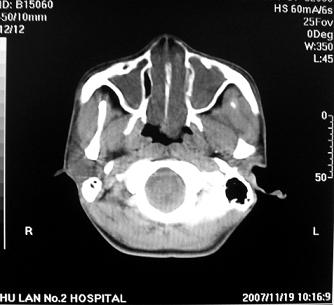

标题: CT10521:男。32岁,副鼻窦ct,请会诊。

男。32岁,鼻塞,流涕一年余。

软组织密度影填满上颌蚪 筛窦及鼻腔,并导致筛骨 上颌窦内侧壁明显骨质破坏。多考虑:内翻性乳头状瘤!

双侧鼻腔内低密度软组织影,骨壁无明显破坏,鼻腔无扩大,双侧上颌窦、筛窦软组织影,窦壁增厚,结合临床考虑鼻息肉合并慢性上颌窦炎。